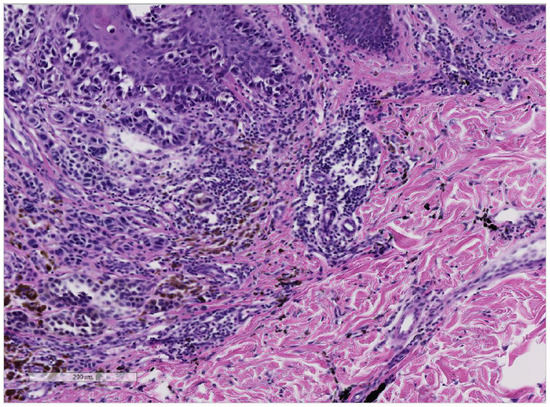

3.1. Cases with the Formation of Melanoma in Tattooed Skin

3.2. Cases with the Formation of Basal Cell Carcinoma in Tattooed Skin